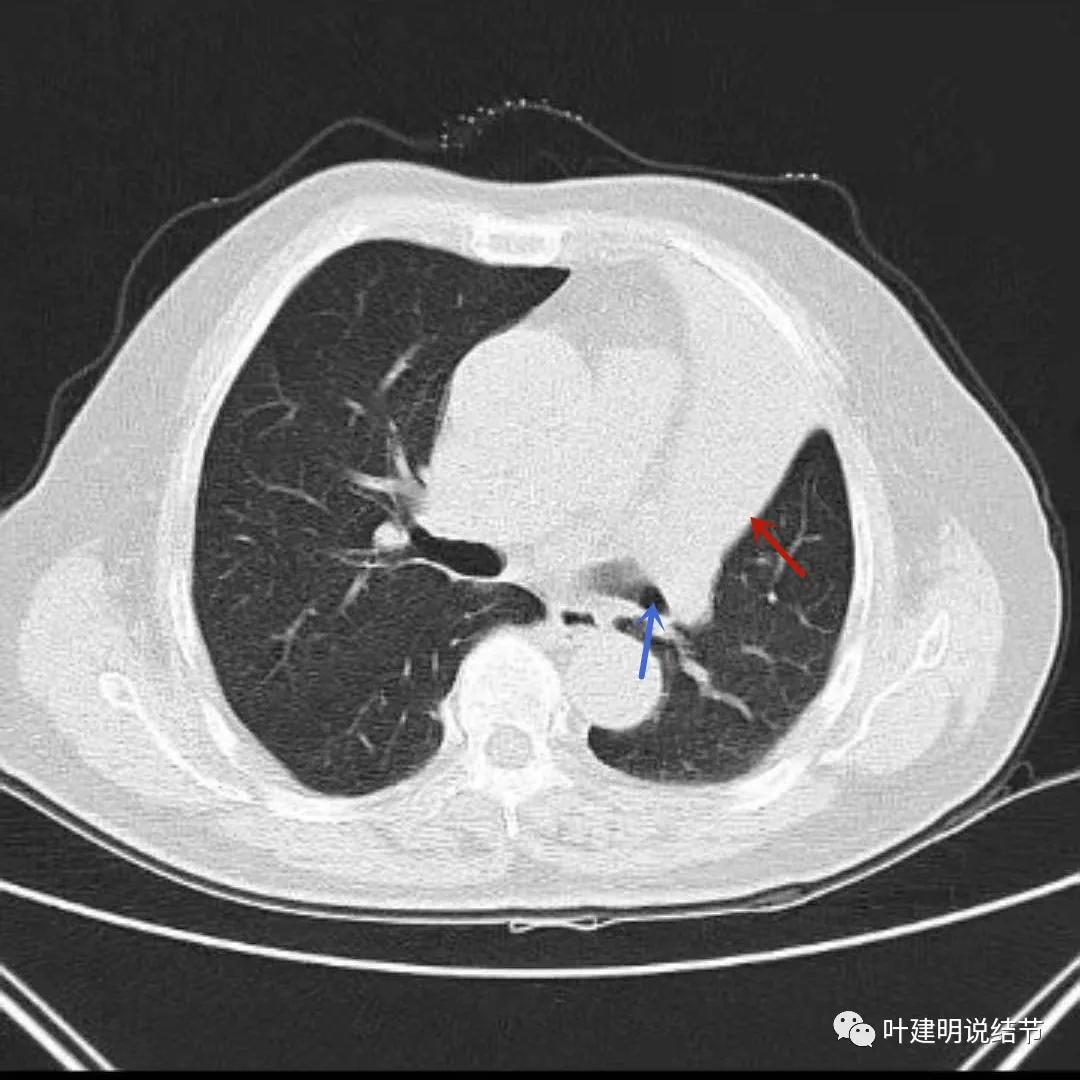

上图与左上叶不张与肿瘤以及蓝色箭头所示的左下叶支气管腔是通畅的

上图示肿瘤、肺不张与下叶支气管